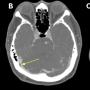

FIGURE 2: MRI images showed (a-c) enlarged and enhancing lymph nodes at levels 2, 3, and 4 of the right cervical neck regions; (d) lobulated soft tissue mass measuring 2.6 cm x 4.9 cm x 6.3 cm in the right pre- and postauricular space

Case Report Page 557 - 562

Recurrent Kimura Disease of the Submandibular Region After Prolonged Remission to Radiotherapy and Its Challenges